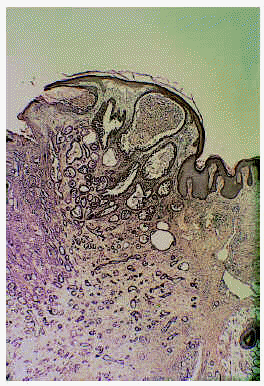

Se trata de un hombre de 26 años de edad que consultó por una lesión localizada en su axila izquierda, que no producía ningún síntoma salvo la molestia inducida por el roce, de unos 8 meses de evolución. En la exploración dermatológica se observó una tumoración eritematosa, excrecente, blanda, bien delimitada y que asentaba sobre una piel de aspecto normal (fig. 1). La lesión fue extirpada quirúrgicamente y sometida a estudio dermatopatológico. Se observó un tumor bien delimitado, con un collarete epidérmico, compuesto por múltiples estructuras tubulares, algunas de las cuales se encontraban aisladas en el seno del tumor, pero otras estaban en relación con invaginaciones epidérmicas en una zona de la lesión (fig. 2). Los túbulos se encontraban embebidos en un estroma marcadamente fibroso y tenían un diámetro muy variable, llegando a adoptar los más dilatados un aspecto quístico (fig. 3). A mayor detalle se observaba que la pared de los túbulos estaba compuesta al menos por dos capas celulares (la externa de morfología cúbica y la interna columnar); en la luz tubular existían proyecciones papilares intraluminales y secreción por decapitación y el estroma tumoral presentaba un rico infiltrado de linfocitos y células plasmáticas (figs. 4 y 5). Este cuadro clinicopatológico fue diagnosticado como ATA, aunque focalmente las imágenes histopatológicas eran indistinguibles de las de un SCAP.

Fig. 1.--Imagen clínica de la lesión.